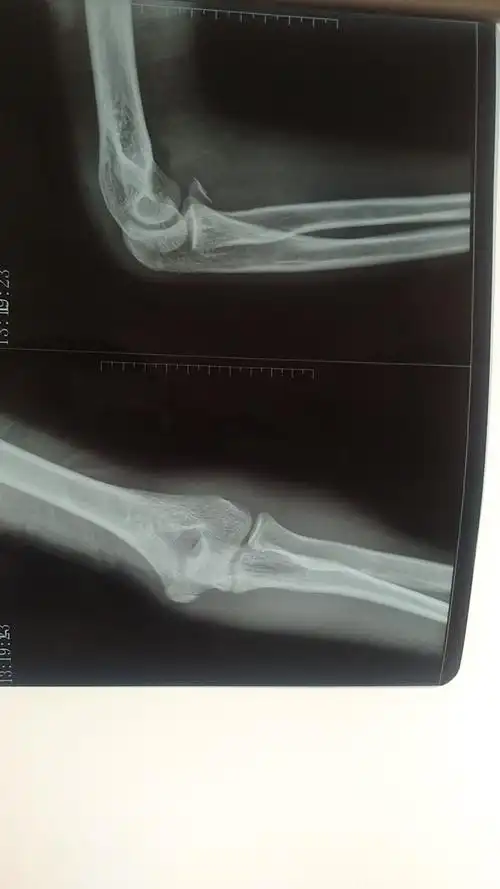

中老年人尺桡骨远端骨折1例分析

尺骨冠突骨折